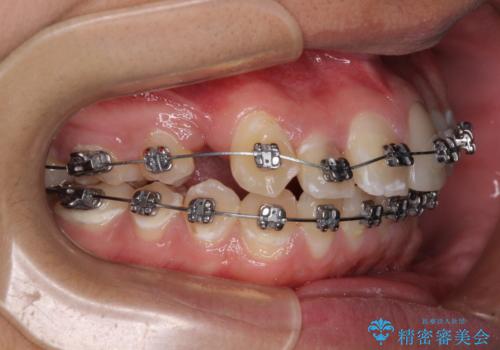

- 矯正装置

- メタルブラケット

- 治療期間

- 2年6ヶ月

むし歯が多かったため、ワイヤー矯正中に処置したむし歯が悪化することが懸念されましたが、歯磨きをしっかりと行ってくれたため、とても良好な状態を維持することができました。